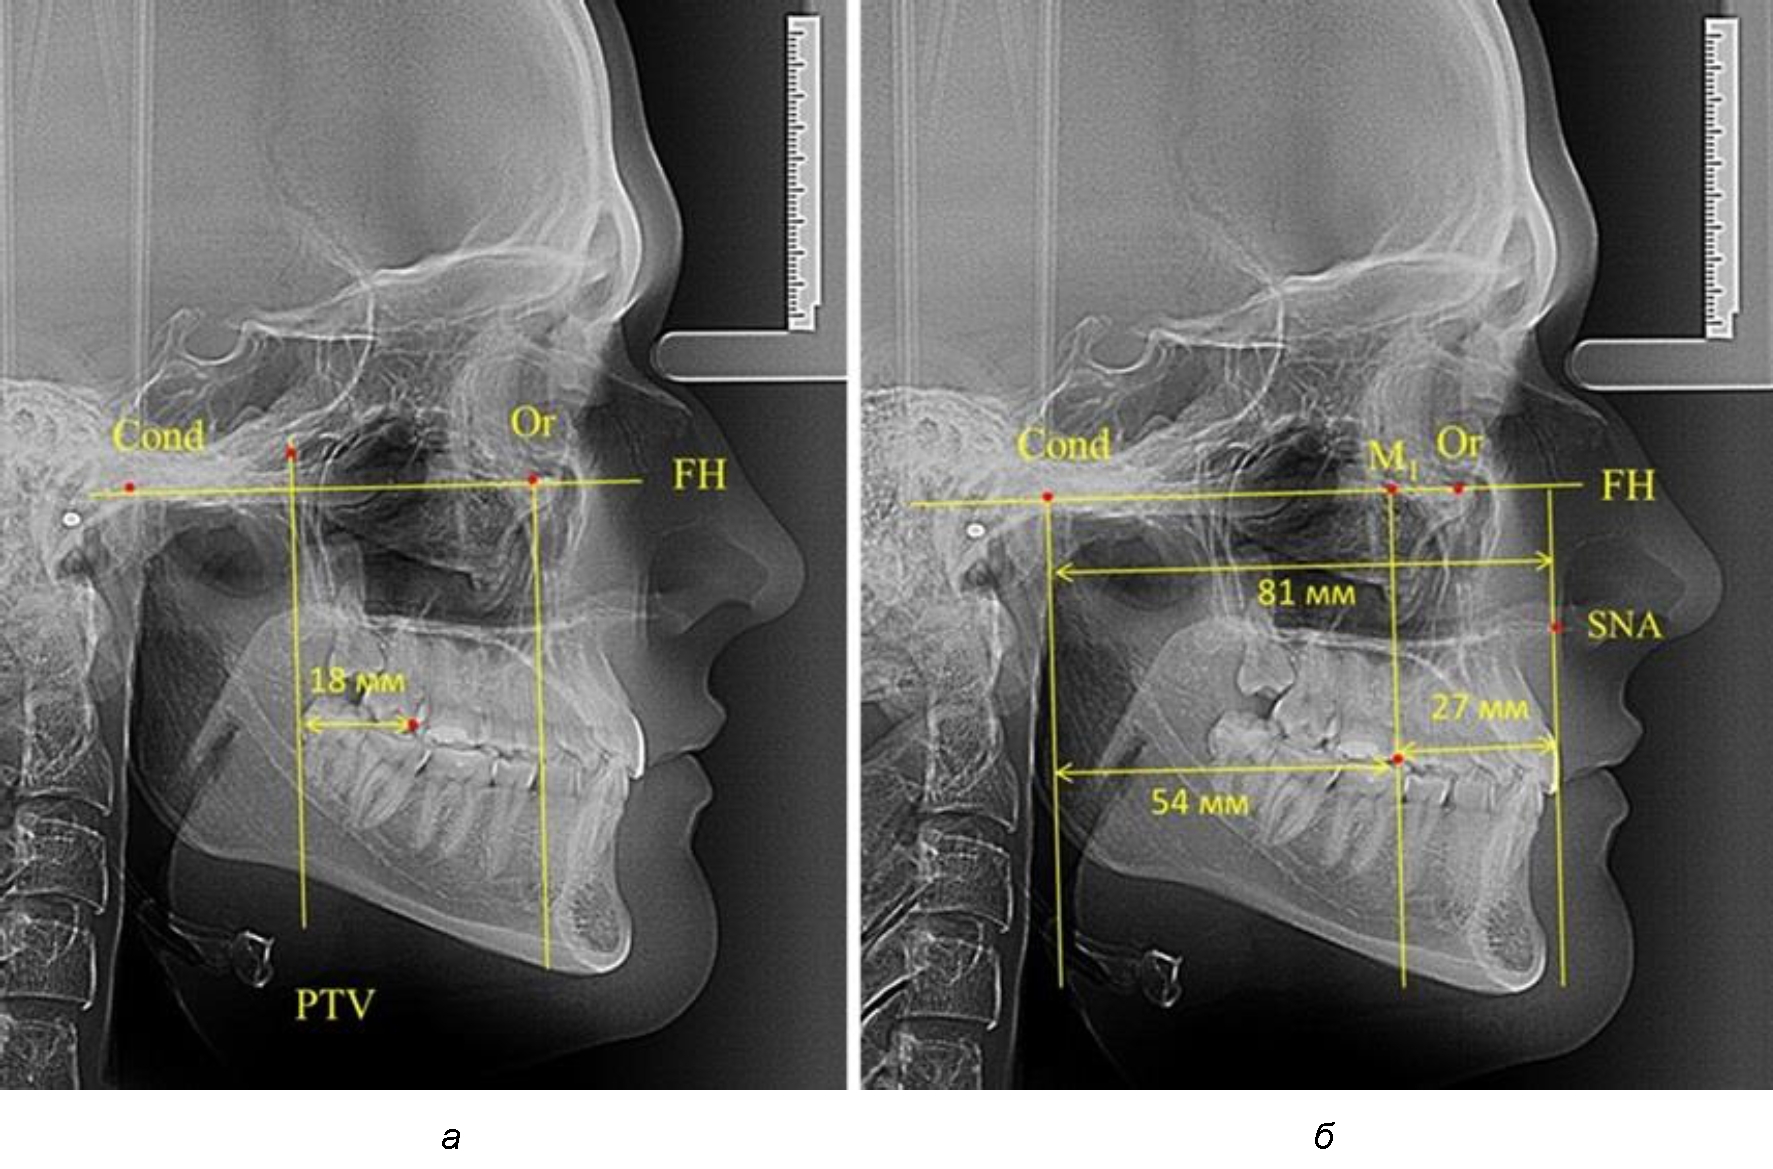

Рис. 2. Особенности положения первых моляров по R. E. McDonald (а) и по предложенному методу (б) при уменьшенном молярно-крыловидном расстоянии

Так, при расстоянии от крыловидной вертикальной плоскости PTV до дистальной поверхности верхнего первого постоянного моляра в 13 мм сагиттальный размер гнатического отдела был 82 мм. При этом отношение кондилярно-спинального расстояния к кондилярно-молярному размеру (54,5) было близким к коэффициенту 1,5, что представлено на рис. 2.

Таким образом, для прогнозирования оптимального положения первых постоянных моляров наиболее целесообразным методом явилось использование относительного показателя, что подтверждено при анализе рентгенограмм с минимальными и максимальными значениями по методу R. E. McDonald.

Таким образом, наблюдалась эффективность использования относительных показателей при определении положения первых постоянных моляров. При этом наиболее целесообразно и с методологической точки зрения верным, было использование медиальной поверхности первого постоянного моляра. Построенная таким образом молярная линия отграничивала отдел зубной дуги с замещающими зубами от дистального отдела с добавочными зубами постоянного прикуса, в частности, постоянных моляров.